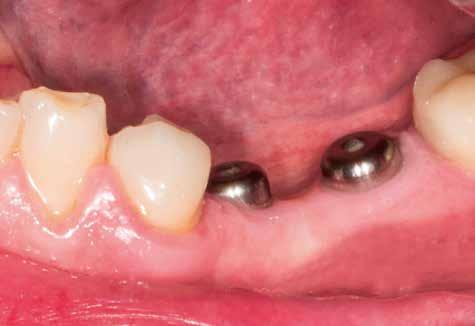

1–2. képek: Kiindulási helyzet.

3. kép: Új teleszkópos fogpótlás az 16, 15, 13, 23 és 27 fogakra.

Teleszkópos munka, élő eset bemutatásával ismertetem, mi az, ami már lehetséges. A munkaasztal-szkenneren kívül bevetésre került a digitális munkafolyamatok során egy intraorális szkenner (IOS) is. A 3D nyomtatású testek gyártása a laboratóriumban LCD- és DLP nyomtatókkal történt. A fémes komponenseket szelektív lézerolvasztásos (SLM) technológiával készíttettük.

4. kép: Intraorális szkennelés Würzburgban, a Biebl&Knapp rendelőben.

Kiindulási helyzet

A páciens látlelete a következő:

• krónikus általános parodontitis

• a 24-től terjedő parodontális fekély

• hatástalan kapcsos felső fogpótlás (1-2. képek)

Terápia

A kezelőorvos (dr. Werner Knapp, Würzburg) ennek alapján a következő terápiát javasolta:

• a 24-es fog extrakciója, illetve az 12 és 22 fogak extrakciója előrehaladott szövetveszteség okán

• szisztematikus parodontitis-terápia

• új, teleszkóp-elhorgonyzású felső fogpótlás az 16, 15, 13, 23 és 27 fogak felhasználásával (3. kép)